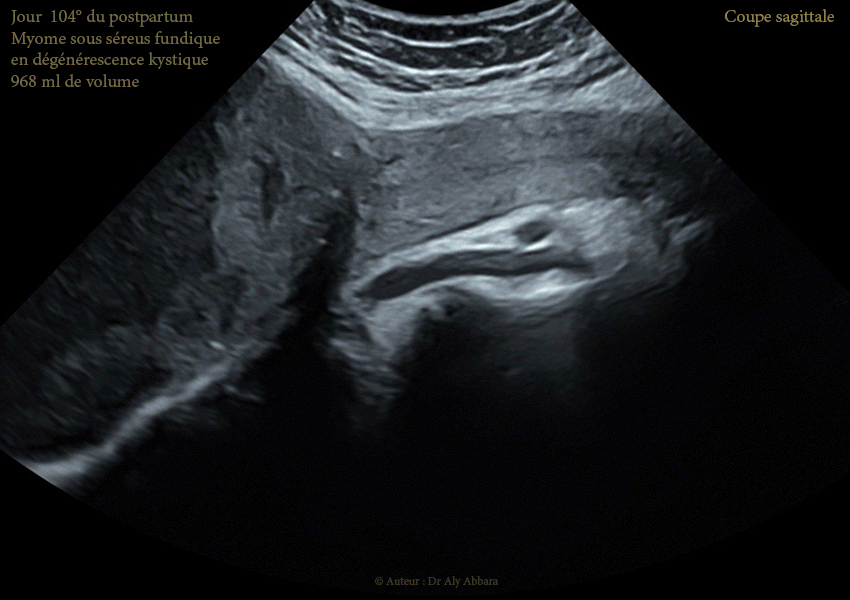

Images échographiques montrant un utérus myomateux portant un myome sous-séreux fundique (classe 7 de la classification FIGO 2011). Images prises au 104ème jour du postpartum après un accouchement par césarienne au terme de 36,5 SA.

Cette régression volumique du myome utérin enkysté s'est poursuivie en postpartum : 1330 cm3 au 3ème jour du postpartum ; 1200 cm3 au 38ème jour du postpartum ; 1119 cm3 au 73ème jour du postpartum et enfin 968 cm3 au 104ème jour du postpartum (~ 15ème jour du postpartum).

Au 104ème jour du postpartum, ce myome apparaît comme une énorme formation kystique de 968 cm3 de volume, vascularisée et attachée à la surface extérieure du fond utérin ; son contenu est trouble, liquidien, hypoéchogène avec des plages d'aspect nuageux liées à la présence de résidus flottants (nécrotiques).

Au jour 104 du postpartum : dégénérescence kystique quasi totale ; décroissance volumique (968 ml).